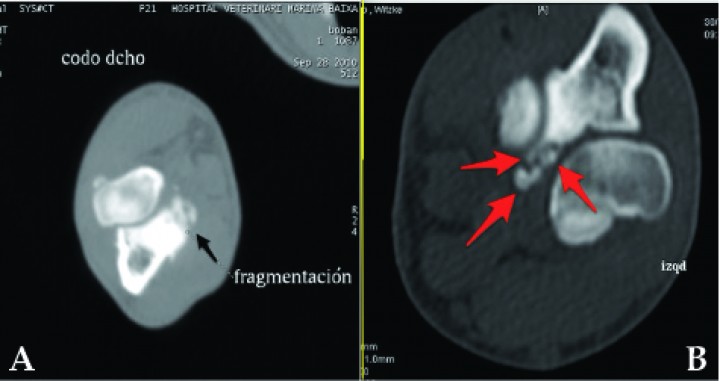

El diagnóstico presuntivo de la displasia de codo y el estudio de la graduación de la misma en la mayoría de animales fue realizado a través de la radiología (Fig. 5).

<p>Radiografía lateral de un Labrador de 11 meses donde se observa una marcada esclerosis subtroclear (flechas amarillas) y difuminación del borde del proceso coronoideo (flechas rojas) indicativas de enfermedad del compartimento medial.</p>

Figura 5

Radiografía lateral de un Labrador de 11 meses donde se observa una marcada esclerosis subtroclear (flechas amarillas) y difuminación del borde del proceso coronoideo (flechas rojas) indicativas de enfermedad del compartimento medial.

Aunque el estudio radiográfico se utiliza como medio de diagnóstico primario de forma generalizada, numerosos estudios cuestionan no sólo su eficacia, sino el valor de los hallazgos.

En los estudios publicados en la literatura de enfermedad coronoidea con un número alto de casos clínicos aportados, el porcentaje de identificación prequirúrgica del EPCM basado solamente en la radiología es muy bajo.[ Fitzpatrick, N. Subtotal coronoid ostectomy (SCO) for the treatment of FMCP: A prospective study of 389 elbows evaluating short and medium term outcome. Proceedings Autumn Scientific Meeting BVOA, Nov 2006, 22-29. ]

La imagen radiológica que lleva al diagnóstico de la enfermedad coronoidea cambia dependiendo de la edad del animal. En los menores de 1 año el signo más visible es una esclerosis subcondral, mientras que en los mayores de un año lo es la difuminación del contorno del proceso coronoides.[ Lau SF, Theyse LF, Voorhout G, Hazewinkel HA. Radiographic, computed tomographic, and arthroscopic findings in labrador retrievers with medial coronoid disease. Vet Surg. 2015;44(4):511-20. [PubMed] ] Igualmente, la eficacia radiológica en el diagnóstico de la enfermedad es un 20% menor en los perros mayores de un año que en los menores de un año.[ Lau SF, Theyse LF, Voorhout G, Hazewinkel HA. Radiographic, computed tomographic, and arthroscopic findings in labrador retrievers with medial coronoid disease. Vet Surg. 2015;44(4):511-20. [PubMed] ]